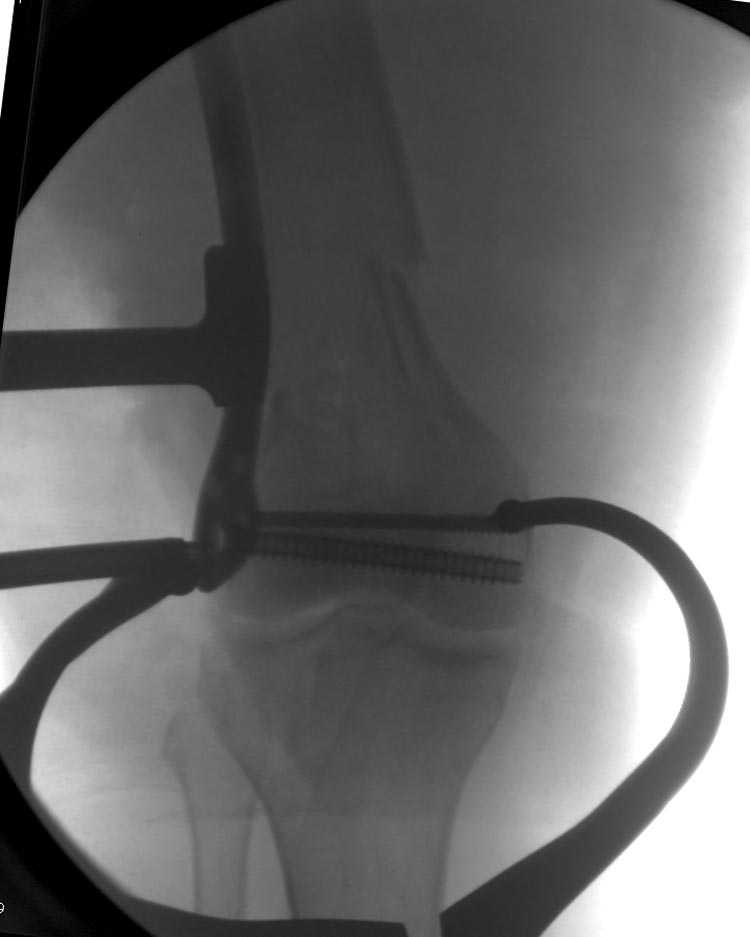

Бесспорно, предлагаемый ретроградный метод имеет свои преимущества, но имеется опасность при манипуляции интрамедуллярным гвоздем расколоть мыщелки.

Раскол можно предупредить шурупами, но короткий дистальный фрагмент навряд ли позволит добиться адекватной стабильности конструкции. Стандартные гвозди не рассчитаны для таких переломов, и если все таки желаете провести фиксацию гвоздем, тогда надо заказывать специальный custom made nail т.е. с расширенной возможностью дистальной блокировки.

Почти все компании имеют пластины с угловой стабильностью, начиная от Stryker, Zimmer NCB и DePuy Polyaxial Plate . Если у NCB шуруп блокируется специальной шайбой, то Polyaxial Plate имеет вариабельный угол введения шурупов.

Поэтому такие меж и над- мыщелковые переломы более предпочтительным считается фиксировать мыщелковыми пластинами

Устанавливается из малого разреза "не вскрывая сустав" со стороны латерального мыщелка, и Insertion Jig позволяет установить пластину "мостовидно" перкутанно в проксимальном отделе, "не вскрывая и не трогая" место перелома.